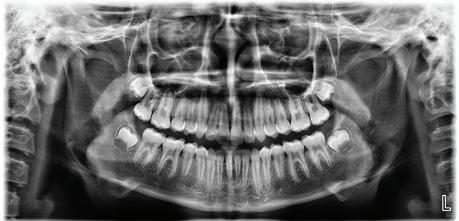

formally know as Northwest Radiography Serving the Seattle area since 1982. Dentofacial Imaging Northwest 1515 116th Ave NE, Suite 108 | Bellevue, WA 98004 425-453-3440 | info@nwrad.com Let Dentofacial Imaging Northwest be your imaging sta ! Same day or next day appointments available! 2D IMAGING • Pan • Ceph • Carpal index • Periapicals • Extraoral bitewings 3D IMAGING • Ortho • Implant planning • Airway studies • TMJ • Location/surgery DENTAL PHOTOGRAPHY • Facial • Intraoral Maximize your space for production by allowing us to house and maintain all your imaging needs.

In 2021, the Swedish Foundation applied for a grant from the Seattle King County Dental Foundation for the final amount needed to purchase a new Sirona Cone Beam CT for the Swedish Community Specialty Clinic

The new CBCT was installed on July 11, 2022 and has already had profound impacts on the quality of care delivered to patients This new machine allows the doctors and staff to take real time, high quality three dimensional imaging in order to rapidly facilitate surgical planning and diagnosis of pathology With the three dimensional imaging, the providers at the Clinic can obtain a precise view of the patient’s hard tissue structure to allow for surgeries to occur more quickly and safely

Prior to the installation of this unit, the patients were required to obtain three dimensional imaging from the medical radiology unit at Swedish First Hill This process was lengthy and tedious for these patients d i ifi tl di upted their access to care